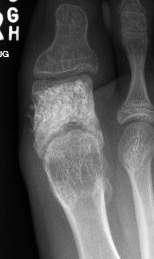

Aneurysmal bone Cyst

Metatarsal metaphysis most common site, followed by calcaneum

Treat with curettage and BG

Can excise an expendable bone like the metatarsal